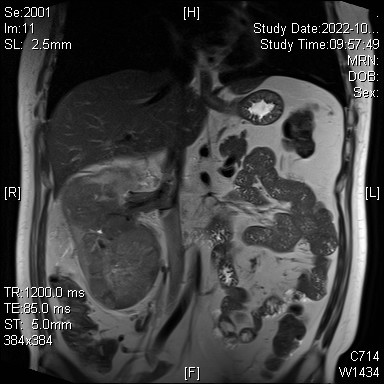

术前MRI示右肾恶性肿瘤并下腔静脉癌栓

泌尿微创二科夏庆华教授团队检查后明确,患者左肾先天性发育不良,功能只有正常的肾脏的1/4,同时合并高血压、高血脂,而且在三年前因心梗放置心脏血管支架,长期服用抗凝药物,不利因素众多。结合宋某的影像学资料,术前诊断为右肾肿瘤并右肾静脉、下腔静脉癌栓(cT3cN0M0,梅奥分级II级),手术风险巨大,可能面临手术中大出血、瘤栓脱落导致肺栓塞可能,手术死亡率极高。